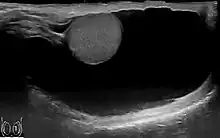

Diagnosis

Through diagnostic ultrasound the accumulation of fluids can be diagnosed correctly.